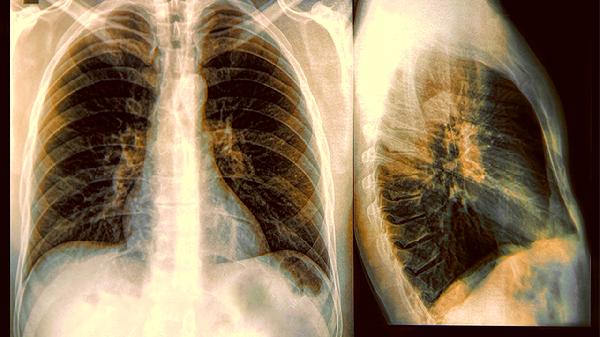

女子肺癌晚期,从不抽烟喝酒,医生问后才知:晚上常做2事

很多人觉得不碰烟酒就能和肺癌绝缘,但生活里藏着不少隐形杀手。一位从不沾烟酒的女士被确诊晚期肺癌时,连医生都感到意外,直到追问出她每晚雷打不动的两个习惯,才揭开了这个健康盲区的真相。